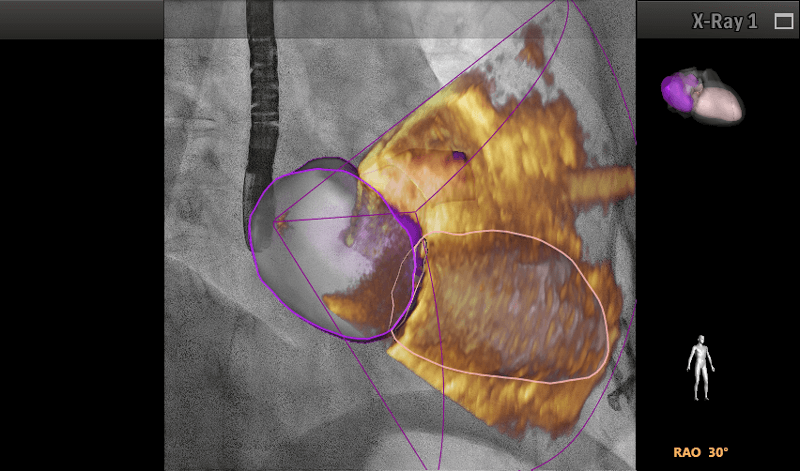

• Cardiología estructural: software de fusión con tomografía y resonancia para colocación de TAVI o cierre de orejuela.

• Estudios congénitos: fusión de imagen con la sonda transesofágica (Echo Navigator).